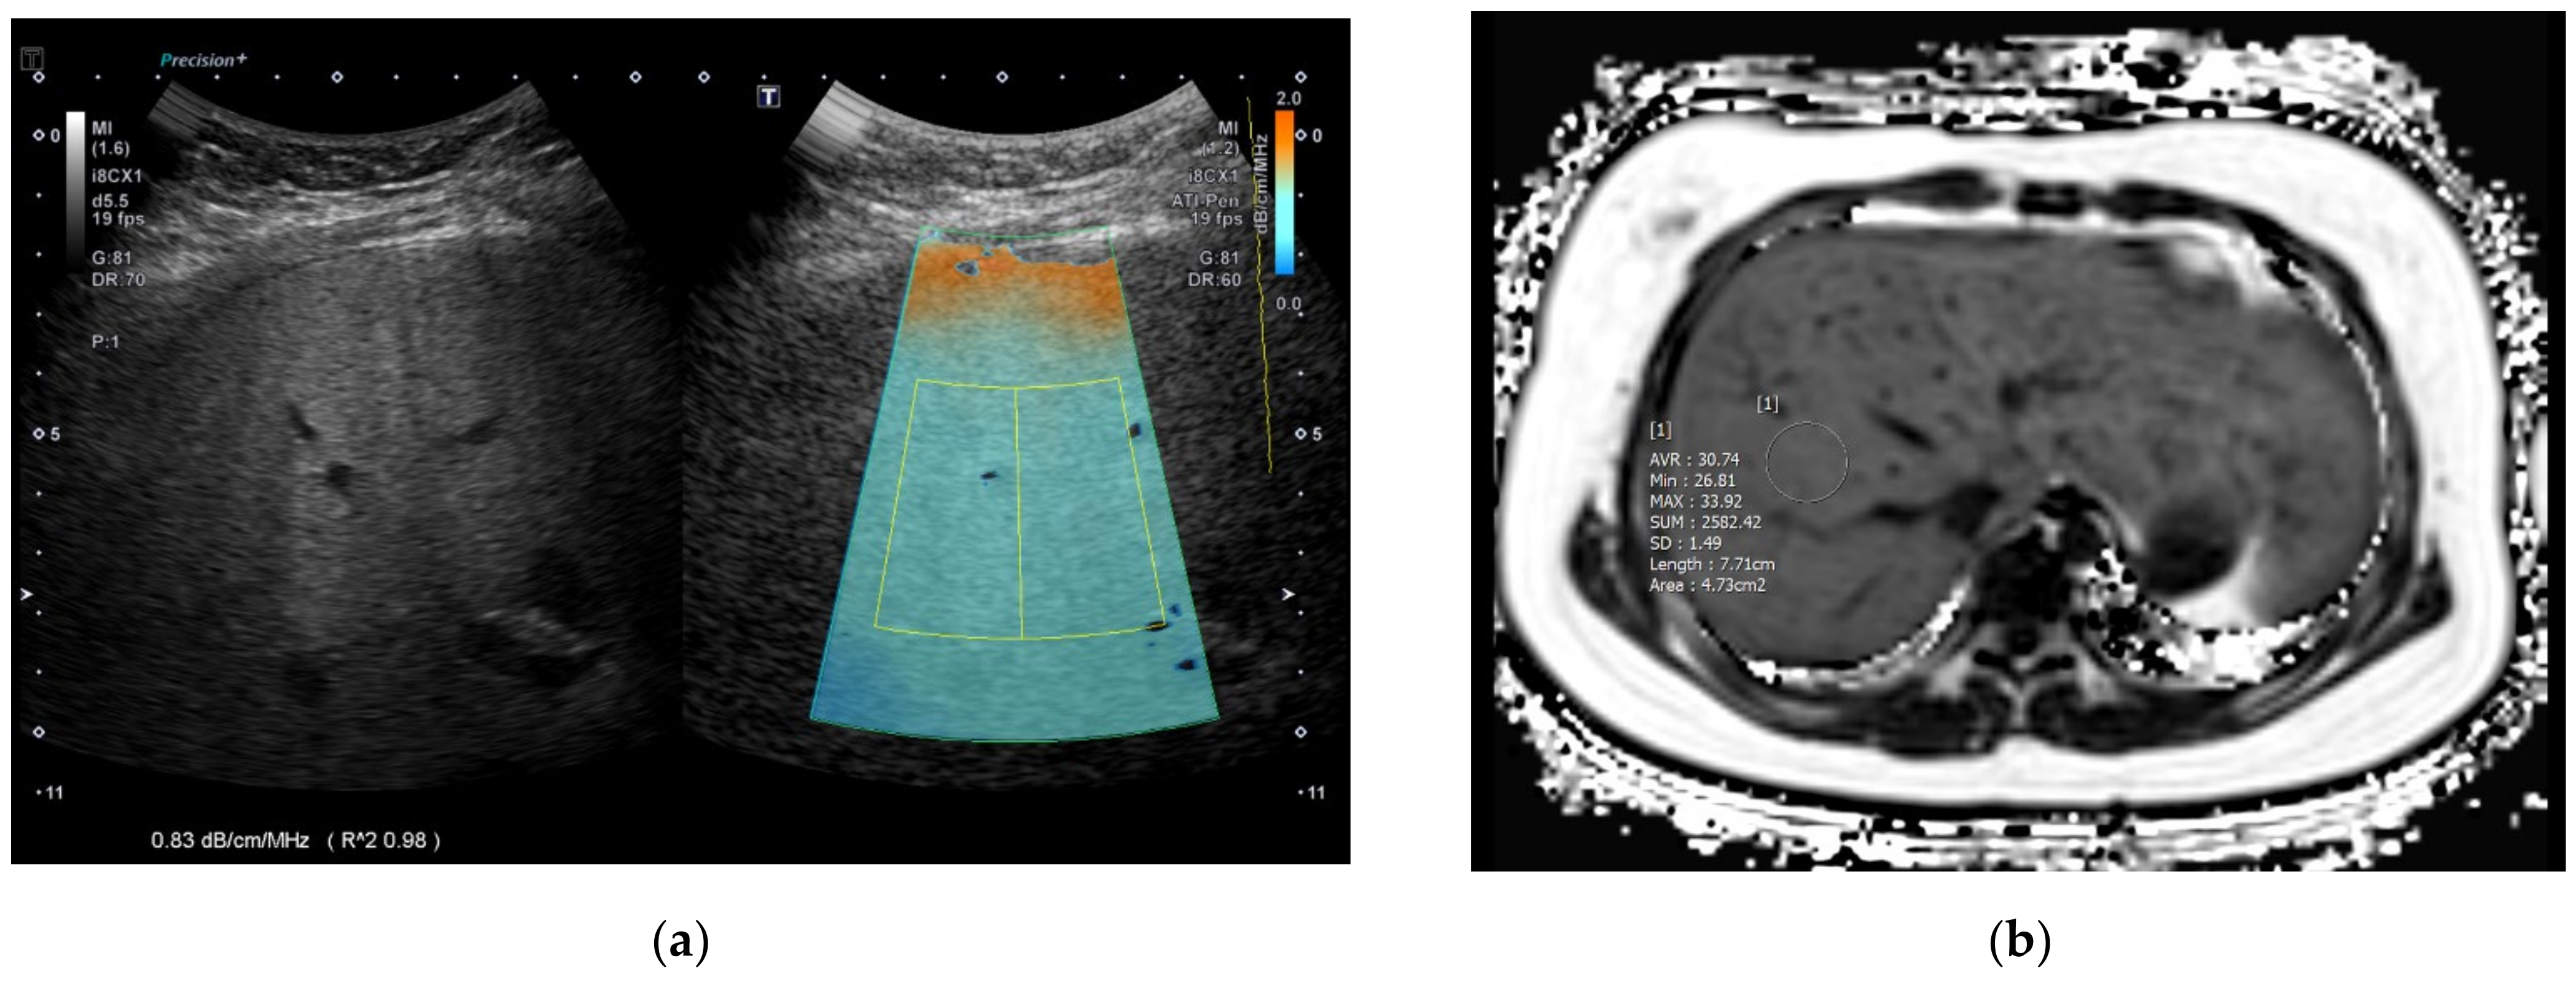

After the acquisition, the maximum longitudinal diameter of the right liver lobe (cm), PDFF (%), T2* (ms) value, and MRE (kPa) value of the liver were collected. To obtain PDFF, T2*, and MRE values, four ROIs were drawn in the liver avoiding hepatic vessels and artifacts using the axial slices of each sequence by an experienced pediatric radiologist and the mean value of the four measurements was used as a representative value (Figure 1 and Figure 2). Steatosis grades could be also categorized using cutoff values of PDFF identified in a previous study; S1 (mild) for PDFF > 6%~<17.5%, S2 (moderate) for PDFF ≥ 17.5%~<23.3%, and S3 (severe) for PDFF ≥ 23.3% [20].

2.3. ATI Acquisition

Figure 2. An 11-year-old girl in the moderate to severe fatty liver group according to grayscale US. (a) The ATI value was 0.83 dB/cm/MHz and (b) MRI-PDFF value was 30.7% (S3: PDFF > 23.3%). US: ultrasonography; ATI: attenuation imaging; MRI: magnetic resonance imaging; PDFF: proton density fat fraction.